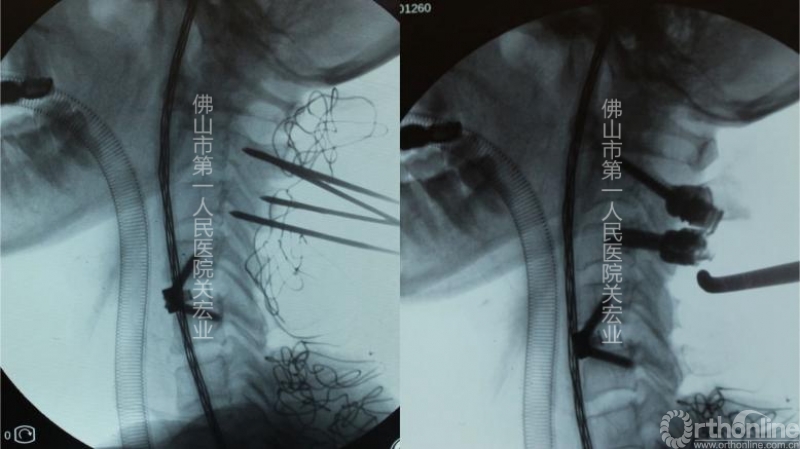

术中操作:

术中置钉与定位